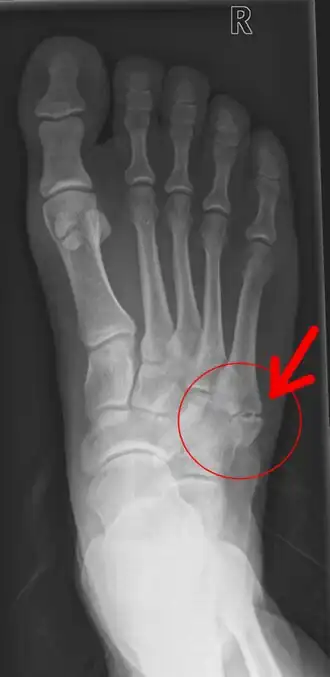

Pseudartrose aan de rechtervoet ter hoogte van het vijfde middenvoetsbeentje (basis metatarsalis V) | ||||

Pseudartrose of pseudoartrose (Grieks: ψευδή, vals, onwaar en άρθρον, gewricht) is het verschijnsel dat optreedt wanneer een botbreuk niet vastgroeit, en er een vals gewricht ontstaat. Wanneer er na zes maanden geen sprake is van consolidatie, dat wil zeggen vastgroeiing, tussen de twee of meer delen van een fractuur, is er sprake van non union en dus van pseudartrose. Als de delen over een periode langer dan vier maanden maar korter dan zes maanden niet vastgegroeid zijn, is er sprake van vertraagde botheling of delayed union.

Bij pseudartrose kan onderscheid worden gemaakt tussen een hypertrofe en een atrofe vorm. De hypertrofe vorm laat wel callusvorming rond de breuk zien, terwijl toch sprake is van non-union. Bij deze fracturen bestaat de therapie met name uit stabiliserende maatregelen. Gipsen of de bothelften middels een plaat of schroeven vastzetten zijn dan de aangewezen therapie. De atrofe vorm van pseudartrose geeft op een röntgenfoto een beeld waarbij het natuurlijke genezingsproces duidelijk achterwege blijft, er wordt dan namelijk geen callus gevormd. Bij deze vorm van pseudartrose moet neovascularisatie op de voorgrond staan. Dit kan worden bevorderd door een spongiosaplastiek uit te voeren, met donorbot of eigen bot van de patiënt uit bijvoorbeeld de bekkenkam. Ook een schroef die enige werking in het bot vertoont (en dus niet geheel vastzit), kan callusvorming bevorderen.